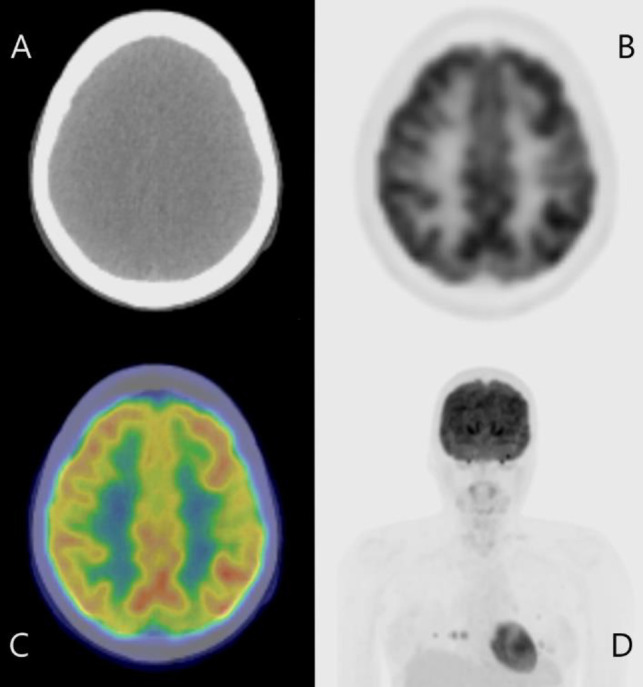

Brain metastasis (BM) occurs only in about 1% of differentiated thyroid carcinoma (DTC) cases. Although DTC generally has a good prognosis, once BM develops, the mortality rate significantly increases up to 78%. BM is usually treated by surgical resection or external radiotherapy, whereas radioactive iodine therapy (RAIT) using I-131 is much less often chosen because BM often shows poor uptake of I-131. In addition, even in case I-131 accumulates in the BM, RAIT could cause adverse effects such as brain hemorrhage and cerebral edema. We present a case of BM from DTC that showed response to I-131 therapy with no severe adverse effects. The brain lesion was very small and asymptomatic, and was only found after a post-therapy I-131 scintigraphy. There are a few case reports where BM was cured by RAIT with little to no side effects. We theorize that BM that is small in size, asymptomatic and show I-131 accumulation could be successfully treated with RAIT.